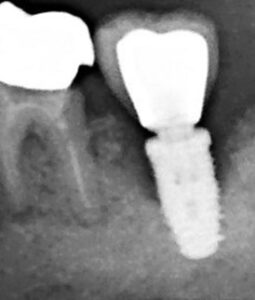

Au stade de « péri-implantite » il s’agit d’une atteinte inflammatoire des tissus mous entourant un implant. Le diagnostic clinique comprend un saignement au sondage, avec une suppuration quasi systématique, et une profondeur de poche péri-implantaire supérieure ou égale à 5 mm. Radiographiquement, un aspect radioclair de déminéralisation osseuse marginale supérieure ou égale à 2 mm entoure une partie plus ou moins étendue du corps de l’implant (fig 1 et 2).

Figure 2: aspect radiographique de la perte osseuse confirmant la péri-implantite